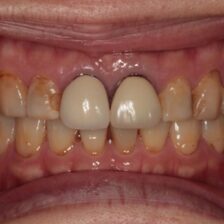

ダイレクトボンディングなどの

審美治療も高精度に対応

当院では、カリーナシステムを活用し、治療前・治療中・治療後の状態を静止画や動画で記録。実際の映像を一緒に見ながら、分かりやすく丁寧にご説明します。